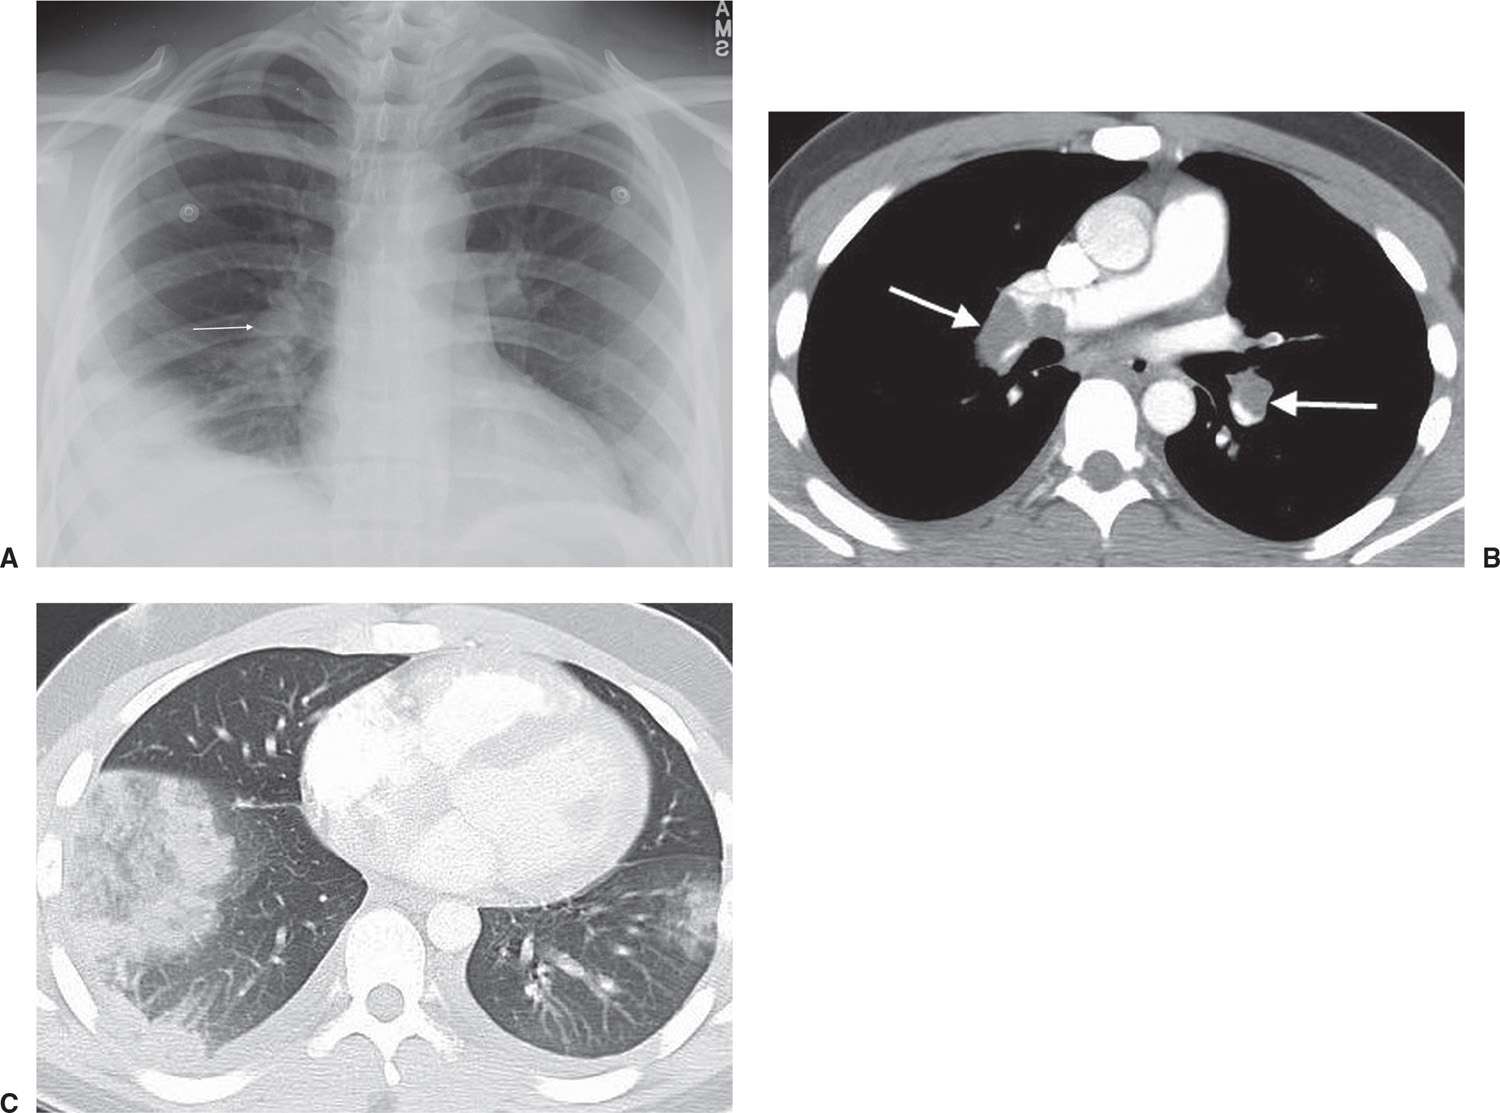

Blunt chest trauma (Swiss cheese sign) (Radiopaedia 3851940618 Axial Swiss Cheese Lungs the term swiss cheese has also been used for the description of pneumatoceles formed with blunt lung. finally, the so called “swiss cheese sign” is used to indicate the appearance that the lung develops with pulmonary tears and pneumatoceles—filled with air and/or fluid after traumatic events. The pneumatocele appears as a “hole” within the lung parenchyma that looks. Swiss Cheese Lungs.